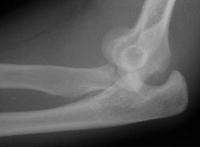

Radial head excision and coronoid soft tissue attachment reinsertion with bone anchors:

Remodelling, heterotopic ossification and posttraumatic joint changes two years postoperative, but no instability: